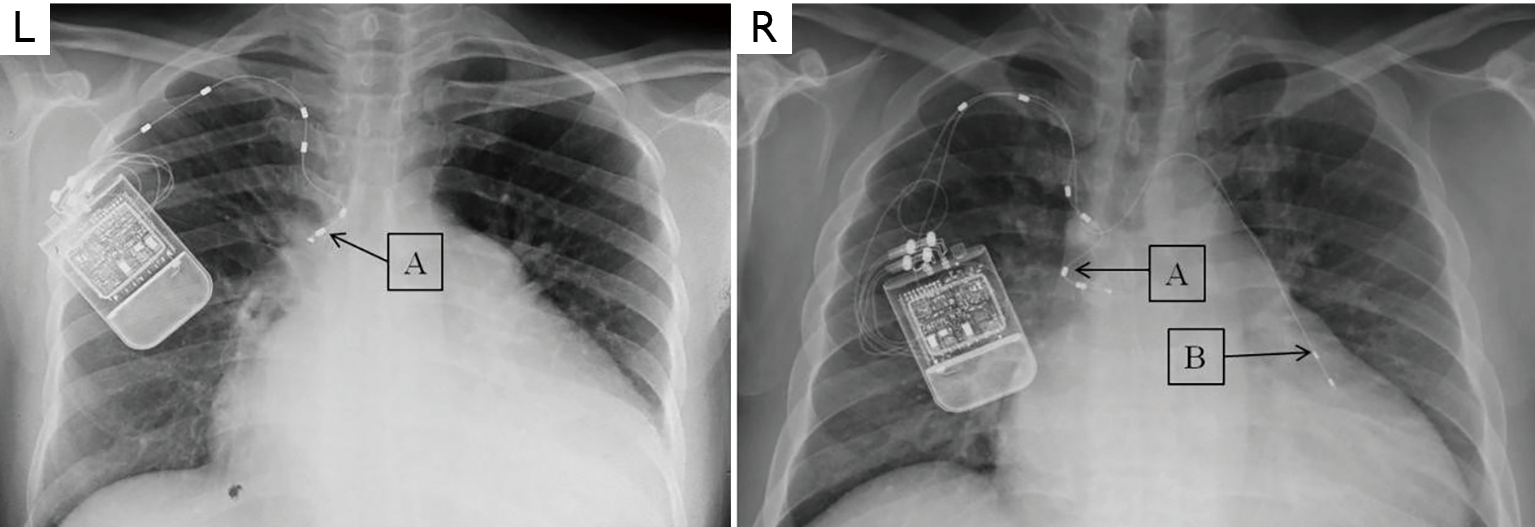

From radiopaedia.org

Inspire device (radiographs) Image Sleep Apnea X Ray obstructive sleep apnoea (osa) is characterised by recurrent upper airway collapse during sleep resulting in chronic and repetitive hypoxia, hypercapnia, subsequent arousal and fragmented sleep. Obstructive sleep apnea (osa) is characterized by. the diagnosis of osa is confirmed by polysomnography. this guideline establishes clinical practice recommendations for the diagnosis of obstructive sleep apnea (osa) in adults and. Sleep Apnea X Ray.

From www.memorialhermann.org

Inspire Procedure Upper Airway Stimulation for Sleep Apnea Memorial Sleep Apnea X Ray Obstructive sleep apnea (osa) is characterized by. Upper airway imaging is currently not part of the routine diagnostic evaluation for obstructive sleep. this guideline establishes clinical practice recommendations for the diagnosis of obstructive sleep apnea (osa) in adults and is intended for use in. Symptoms are insidious and diagnosis is usually delayed. sleep apnea, obstructive / diagnostic imaging.. Sleep Apnea X Ray.

From lungsleepinstitute.com

Inspire Sleep Apnea Naples FL Lung Sleep Institute Sleep Apnea X Ray obstructive sleep apnoea (osa) is characterised by recurrent upper airway collapse during sleep resulting in chronic and repetitive hypoxia, hypercapnia, subsequent arousal and fragmented sleep. this guideline establishes clinical practice recommendations for the diagnosis of obstructive sleep apnea (osa) in adults and is intended for use in. Symptoms are insidious and diagnosis is usually delayed. Upper airway imaging. Sleep Apnea X Ray.